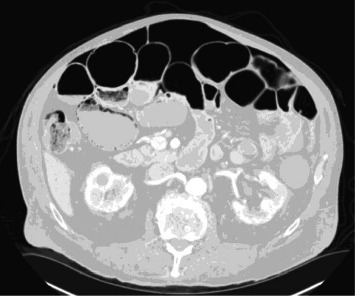

We present our experience with a patient with acute-on-chronic asymptomatic pneumoperitoneum with spontaneously resolving idiopathic pneumatosis intestinalis that was solely managed on close observation alone. This case is unique in that it details the approach to nonoperative management of massive free air under the diaphragm identified incidentally on routine preventative health screening and longitudinal follow-up over an 8-month period. In the absence of known and underlying systemic disease, efficient and coordinated clinical work-up and evaluation for comorbid diagnoses associated with pneumoperitoneum can serve to guide management and avoid unnecessary surgery for stable and asymptomatic patients.